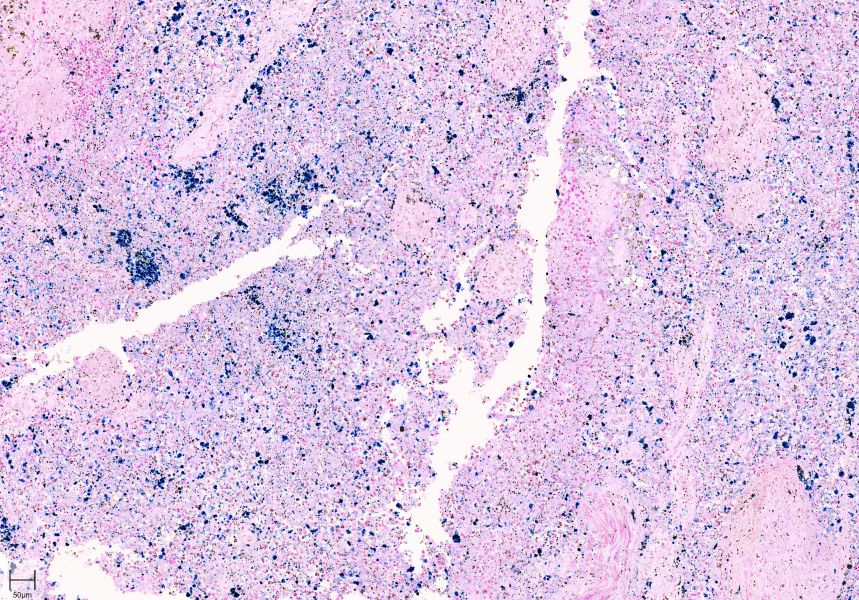

普鲁士蓝染色